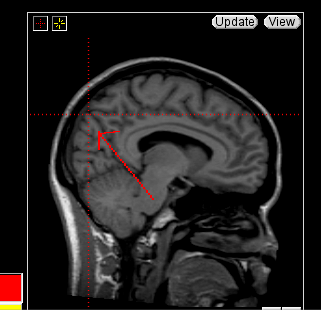

The insular cortex is “hidden” between the temporal and inferior parietal corticies. By drawing sulci lines in the sagittal view, we gain an outline of it in the coronal. Choose a sagittal slice where insula is clearly visible (Fig 1), then draw a “circle” around it (Fig 2). Do this for several slices and for both hemispheres.

Figure 1              Figure

2